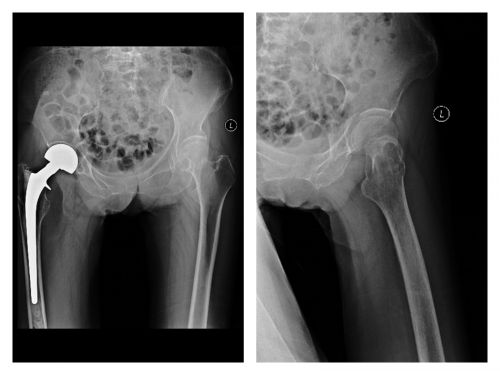

术后复查x线。

在盛斌主任、秦梅兰护士长等医护人员的精心准备及护理下,由王愉思主任、盛斌主任、王海博士等组成的手术小组于2月8日为老人施行左侧人工股骨头置换手术。手术过程顺利,老人术后三天即可下地行走,对出院后的日常生活基本没有影响。